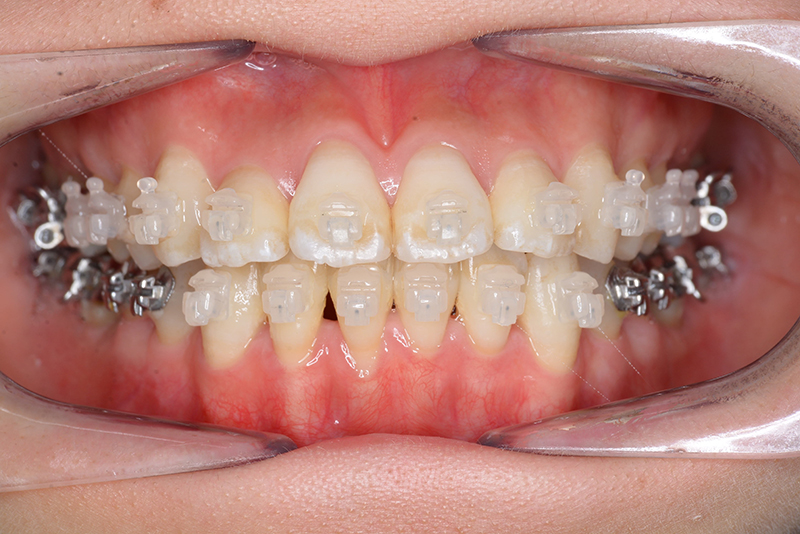

使用装置 0.018" × 0.025" standard edgewise

装置料 プラスチックブラケット(30万円)

口腔内ゴムの使用 Class 5ヵ月、Up&Down 6ヵ月